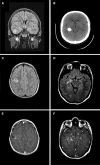

Epileptogenic tumors affecting children and young adults are a morphologically diverse collection of neuroepithelial neoplasms that, as a group, exhibit varying levels of glial and/or neuronal differentiation. Recent advances in molecular profiling technology, including comprehensive DNA sequencing and methylation analysis, have enabled the application of more precise and biologically relevant classification schemes to these tumors. In this report, we describe a morphologically and molecularly distinct epileptogenic neoplasm, the polymorphous low-grade neuroepithelial tumor of the young (PLNTY), which likely accounts for a sizable portion of oligodendroglioma-like tumors affecting the pediatric population. Characteristic microscopic findings most notably include infiltrative growth, the invariable presence of oligodendroglioma-like cellular components, and intense immunolabeling for cluster of differentiation 34 (CD34). Moreover, integrative molecular profiling reveals a distinct DNA methylation signature for PLNTYs, along with frequent genetic abnormalities involving either B-Raf proto-oncogene (BRAF) or fibroblast growth factor receptors 2 and 3 (FGFR2, FGFR3). These findings suggest that PLNTY represents a distinct biological entity within the larger spectrum of pediatric, low-grade neuroepithelial tumors.